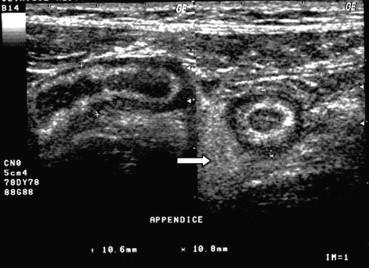

Çocukluk çağlarında karın ağrısı en sık şikayetlerden birisidir. Hayatın ilk 6 ayında en sık karın ağrısı sebebi bağırsak gelişiminin henüz tam olarak tamamlanmadığı için oluşan kolik ağrılardır. Bu durum hemen hemen her bebekte görülmekle birlikte rutin bir karın ultrasonu ile bebekte karın ağrısı sebebi olabilecek başka problem olmadığının teyit edilmesi gerekmektedir. Yine hayatın erken dönemlerinde daha sıklıkla karşılaştığımız bir diğer karın ağrısı sebebi invajinasyondur. Bu durumda bağırsak iç içe girer. Eğer kendiliğinden ya da medikal tedavi ile açılmazsa cerrahi olarak bu lokalizasyondaki problemin çözülmesi gerekebilir. Daha büyük çocuklarda özellikle karnın sağ alt kesimindeki ağrılar yine sık gördüğümüz ağrı lokalizasyonudur. Bu ağrılarda ilk planda akut apandisit ya da mezenterik lenfadenit düşünülür. Genellikle bu iki hastalıkta benzer şikayetlere yol açar. İki hastalığın ayırıcı tanısı ultrason ile kolaylıkla yapılabilir. Bu durumlarda ultrason ile bu ayırıcı tanının yapılması tedavinin şeklini de belirleyecektir. Çünkü akut apandisitte acil cerrahi gerekirken mezenterik lenfadenit antibiyotik kullanarak tedavi edilir.